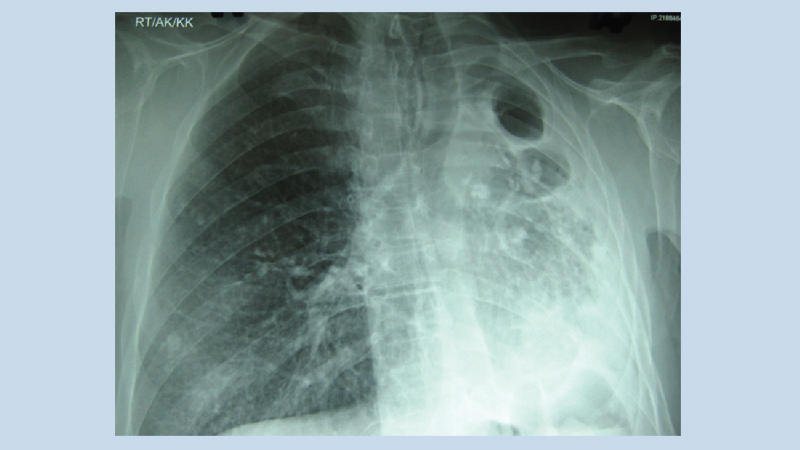

While appointing maids and domestic helpers in the house, one must get them medically examined and regularly subject them to medical examination every year. If a complete medical examination is not possible due to some reasons, the least one can do is to get their chest x-ray and sputum examination done before allowing them to work inside the house and show their investigation results to your family physician or a local physician and solicit his opinion. If your domestic helper or your driver is suffering from dry cough or while coughing passes out large amount of phlegm and spit out blood during coughing, do not sit idle and get the chest x-ray and investigation of blood and sputum and seek advice of your personal physician.

Suspect the possibility of T.B. infection, If anyone of your family members is suffering from fever with daily evening rise in body temperature, sweating, extreme fatigue, weakness, loss of appetite, loss of weight, and feeling of always being sick.. Immediately subject him to investigations of blood and chest x-ray and show them to a local physician.

If any of your family member have a complaint of chest pain which increases in intensity after taking a long breath or pain appears below the shoulder during coughing or there is a complaint of breathlessness while walking or during sitting, one should suspect strongly about the possibility of T.B. infection and initiate steps in that direction.

If a tubercular infection had destroyed the lung partially or completely, immediately consult a Thoracic or a Chest surgeon and get the destroyed part of the lung removed through the operation otherwise the remaining healthy portion of the lung or the healthy lung of the other side will gradually be infected by T.B. and will lead to fatal complications.